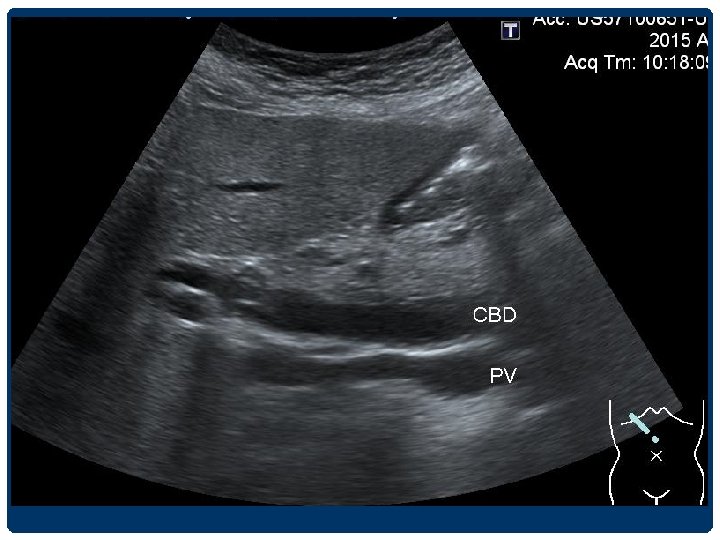

BILIARY DILATATION Extrahepatic duct - CHD 4 -5 mm - CBD วดจากขอบดานในของดานหนงไปอกดานหน ง 4 -6 mm 6 -7 mm equivocal >8 mm indicate ductal dilatation • Elderly patients and in postcholecystectomy patients อาจพบ common duct dilatation ไดถง 9 -10 mm • Acute, intermittent, and partial obstruction

DILATED CBD